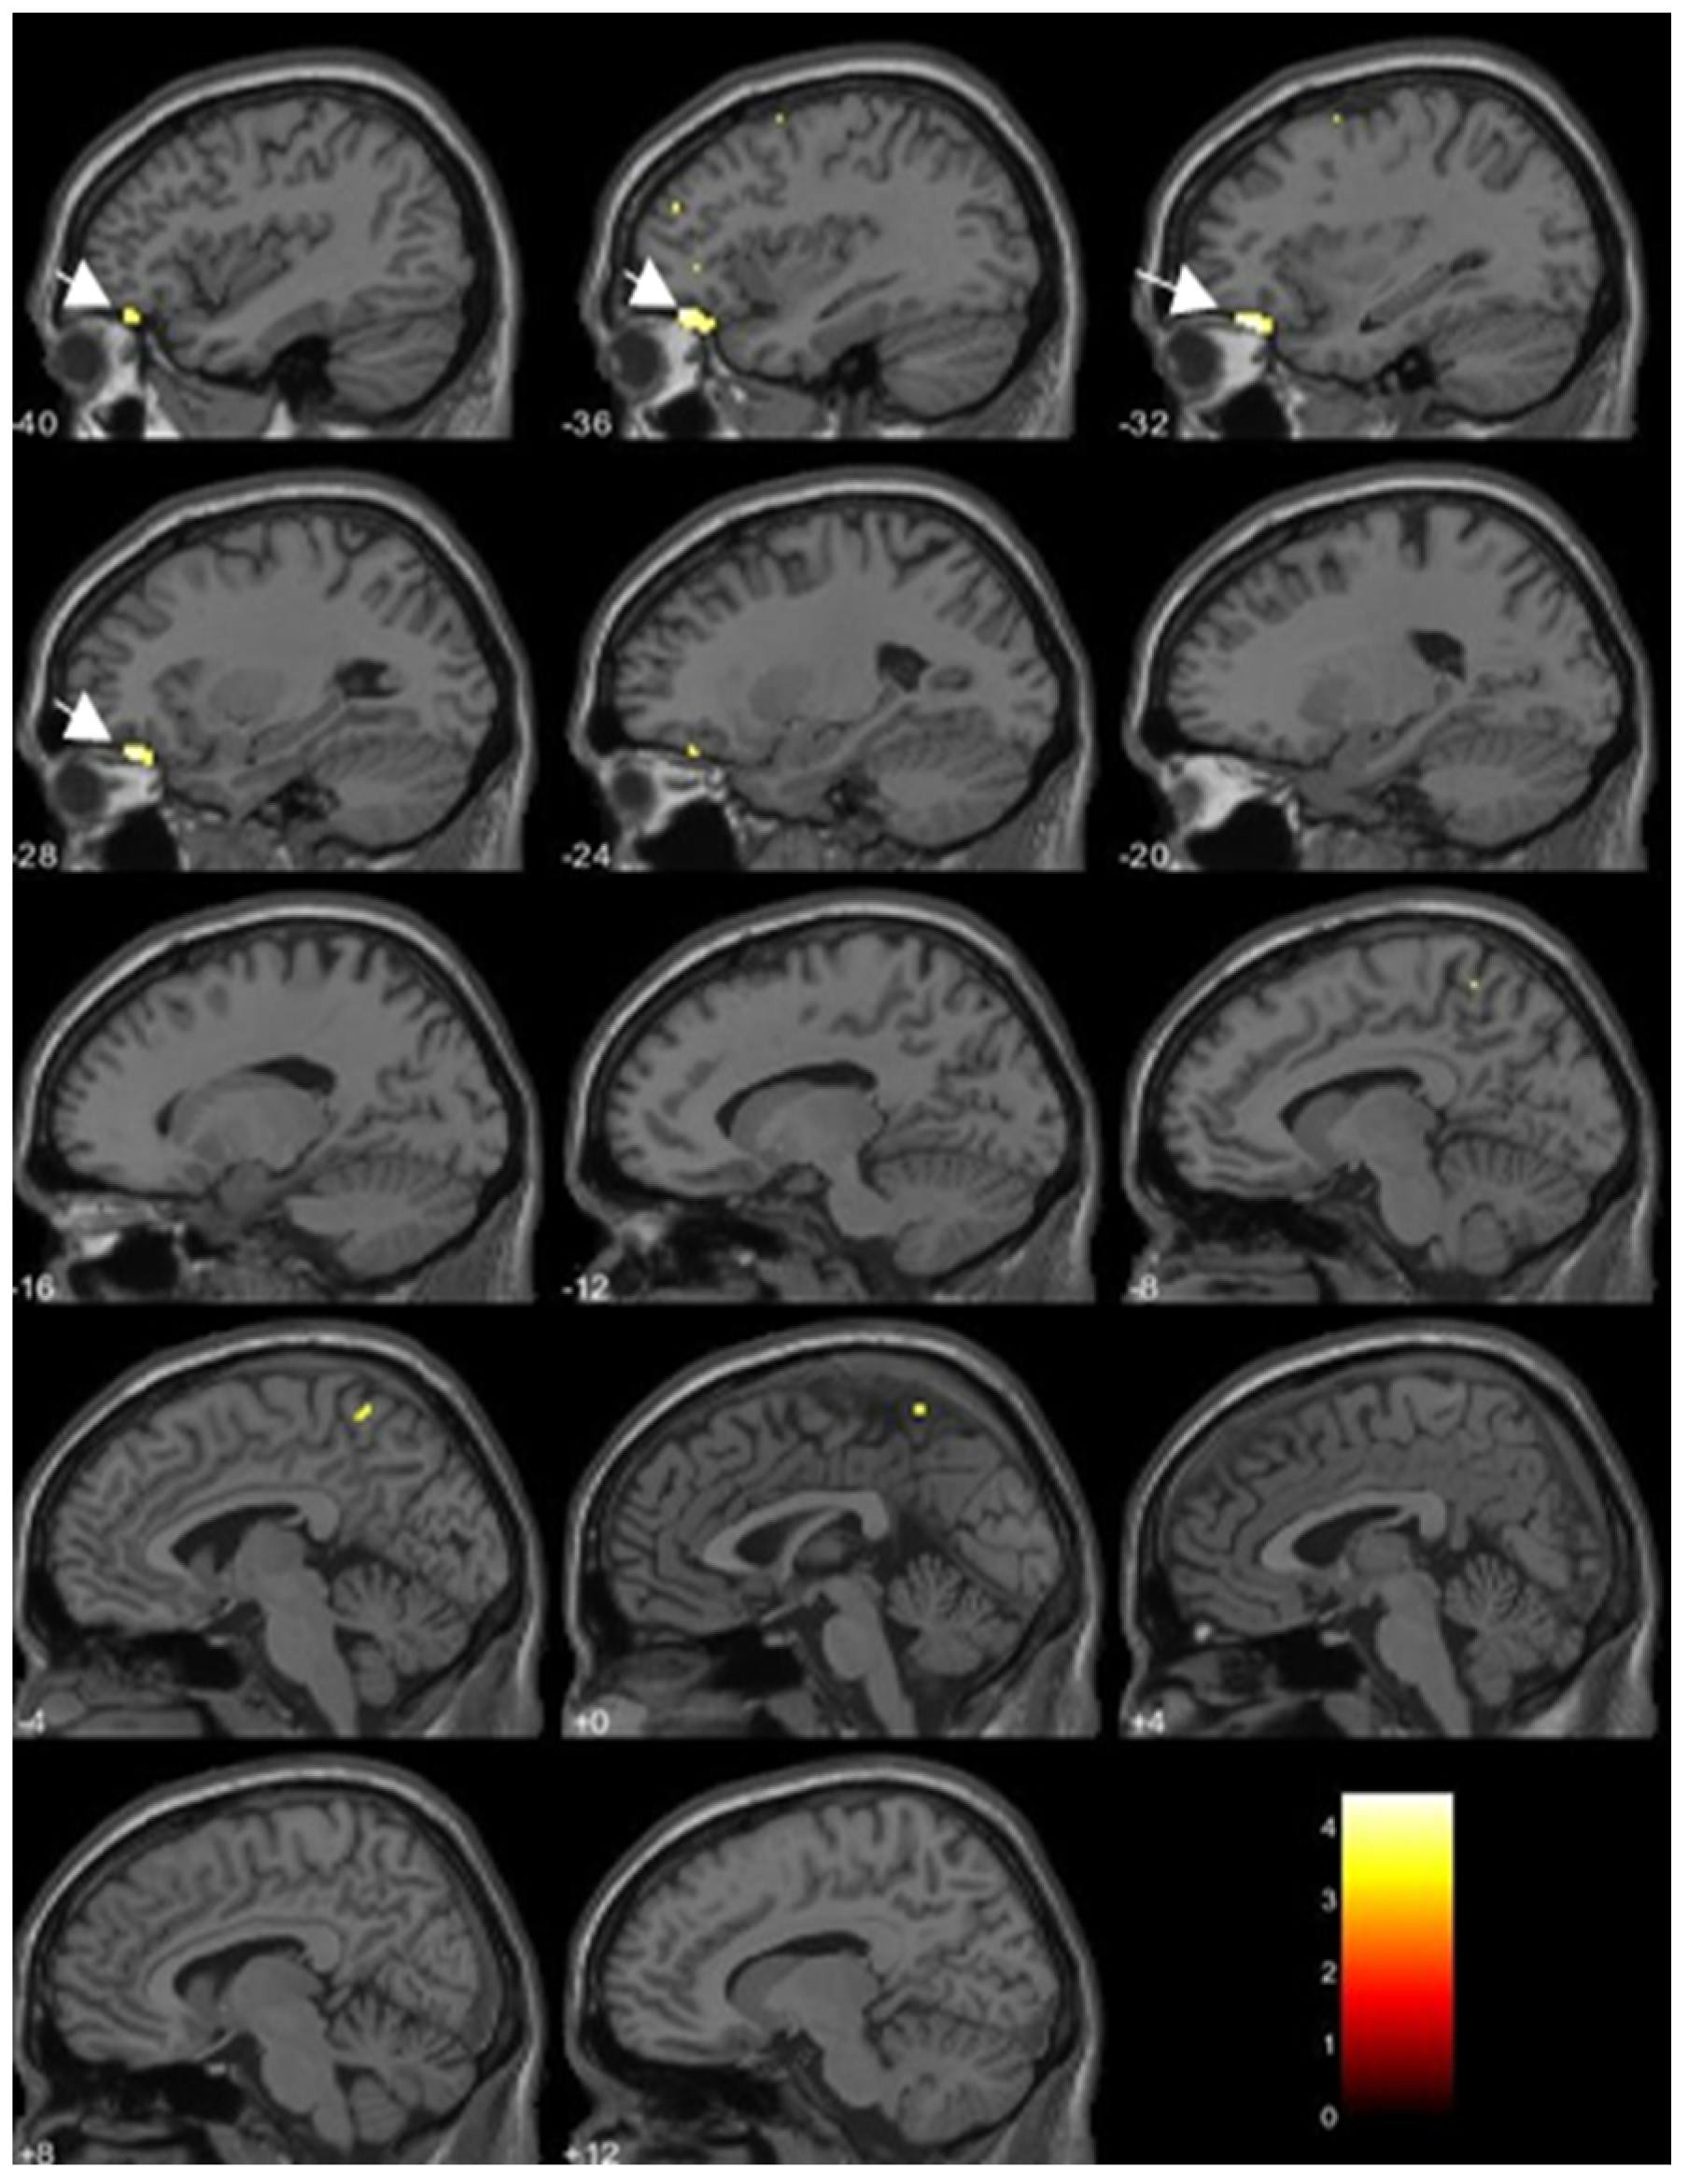

| Inverse correlations | ||||||

| TCDD | Anterior temporal cortex | 905 | ||||

| (Left medial temporal pole) | 3.81 | −41 | 20 | −38 | ||

| (Left fusiform gyrus) | 3.90 | −27 | 8 | −47 | ||

| TEQ-PCDDs | Left medial temporal pole | 333 | 3.63 | −39 | 21 | −38 |

| Positive correlations | ||||||

| 1,2,3,4,7,8-HxCDD | Left cerebellum lobule VII | 373 | 3.87 | −42 | −60 | −57 |

| Right middle frontal gyrus | 505 | 3.86 | 41 | 6 | 60 | |